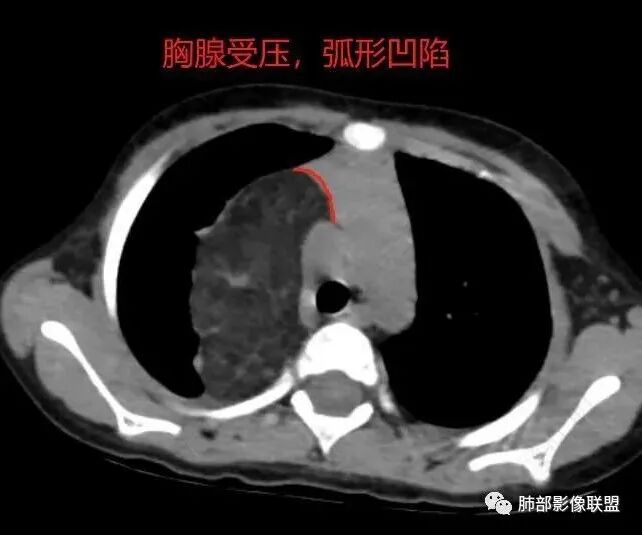

右纵隔团状,密度不均,脂肪密度为主,内可见腺体样组织,类似乳腺,病灶边缘有分叶,与胸腺关系密切,增强后血管穿行。考虑胸腺脂肪瘤(不典型垂乳征),鉴别畸胎瘤。

病灶属于交界区,主体位于肺内,占位效应明显,前方突入胸壁,胸腺受压变形,胸膜显示欠清楚;病灶包绕上叶肺动脉;似乎有体动脉供血。符合肺内的点:包绕上叶肺动脉分支;符合纵隔的点:前方似乎突入胸壁,与胸腺关系比较密切,但是与上腔静脉的关系提示病灶不支持纵隔来源,前纵隔的常规会将上腔静脉受压后移、外移,这是不符合的。

1.右上肺-纵隔交界区巨块影,主体位于右肺一侧,紧贴胸腺、头臂干、右锁骨下动脉、上腔静脉、奇静脉等,不能分离,但病灶整体边界清楚。注意上述相邻腔静脉等结构未见受压变形,纵隔亦未见明显向左推移,至少提示两点:

1)病灶相当柔软。

2)位于纵隔内或纵隔胸膜的可能性较小,因为受纵隔胸膜反作用力影响不明显。